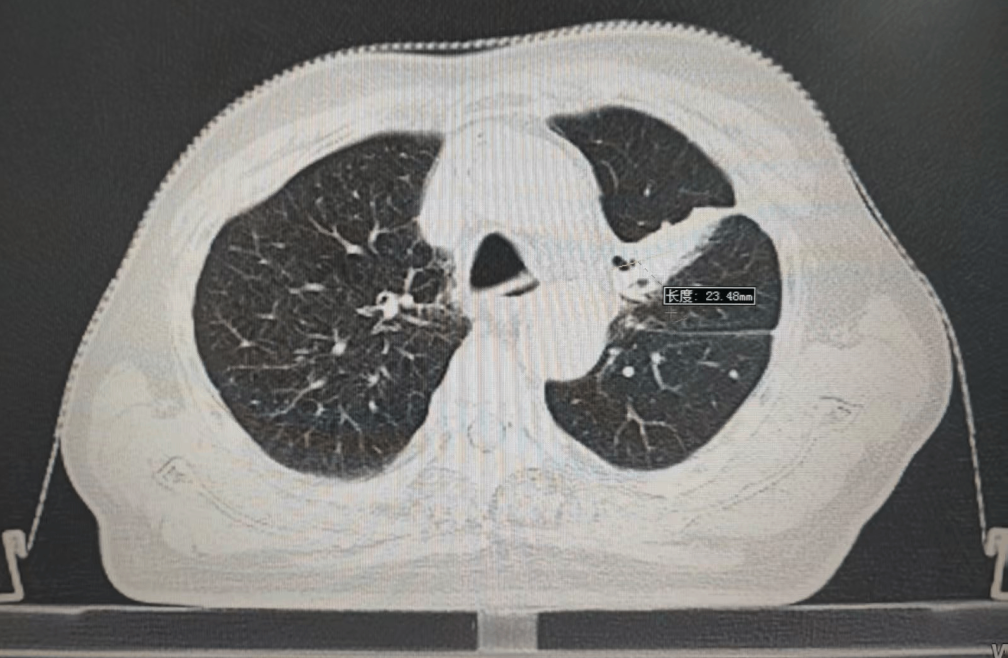

內(nèi)容提要 PART. 01 高齡抗癌的“生死抉擇” 當(dāng)6.7cm腫瘤遇上80歲身體 四年前,李大爺因乏力、消瘦、氣短等癥狀,意外發(fā)現(xiàn)左肺巨大占位,大小約6.7cm×4.9cm,最終在北京大學(xué)腫瘤醫(yī)院確診為肺鱗癌。面對(duì)82歲高齡和腫瘤的兇猛進(jìn)展,家屬一度陷入絕望,并決定回到家鄉(xiāng)醫(yī)院尋求治療方法。 治療前腫瘤影像 “開(kāi)胸手術(shù)風(fēng)險(xiǎn)極高,傳統(tǒng)化療對(duì)肺鱗癌效果有限,還可能加重身體負(fù)擔(dān)?!蓖醮簭?qiáng)主任回憶,團(tuán)隊(duì)當(dāng)即決定采用局部精準(zhǔn)放療,在確保療效的同時(shí),最大限度減少對(duì)正常組織的損傷,提高生活質(zhì)量,為老人開(kāi)辟一條生路。 PART. 02 四年抗癌“成績(jī)單” 腫瘤縮小70%,生活如常 治療的關(guān)鍵在于“毫米級(jí)”的精準(zhǔn)打擊。依托國(guó)內(nèi)頂尖放療設(shè)備——美國(guó)瓦里安直線加速器,團(tuán)隊(duì)通過(guò)三維適形調(diào)強(qiáng)放療技術(shù)(IMRT),將放射線誤差控制在1mm內(nèi),既集中火力攻擊腫瘤,又能降低周?chē)谓M織損傷。配合PET/CT生物靶區(qū)動(dòng)態(tài)追蹤技術(shù),醫(yī)生能清晰區(qū)分活躍癌細(xì)胞與壞死組織,實(shí)時(shí)調(diào)整治療方案。 四年間,李大爺?shù)哪[瘤病灶持續(xù)縮小,從最初的6.7cm縮小至目前的2.3cm,氣短癥狀顯著改善,治療期間甚至未出現(xiàn)放射性肺炎等并發(fā)癥。如今的他不僅生活完全自理,還活躍于社區(qū)老年活動(dòng),焦慮評(píng)分從重度降至幾乎消失。 治療后腫瘤影像 “很多患者以為抗癌就是‘你死我活’,其實(shí)‘帶瘤生存’同樣能創(chuàng)造生命價(jià)值。”這場(chǎng)“生命奇跡”的背后,是市二院放射治療中心對(duì)精準(zhǔn)醫(yī)學(xué)的深刻踐行,科室憑借超高的技術(shù)水平及一批國(guó)際頂尖設(shè)備支持,不斷提升生物靶區(qū)勾畫(huà)精度,并建立多學(xué)科診療(MDT)模式,融合外科、靶向、免疫、粒子等手段,為200余例高齡腫瘤患者制定個(gè)性化方案,顛覆了“高齡癌癥等于絕癥”的傳統(tǒng)認(rèn)知。 PART. 03 人民醫(yī)院 人民名醫(yī) 王春強(qiáng) 副主任醫(yī)師 ·葫蘆島市第二人民醫(yī)院放射治療中心主任 ·原中國(guó)人民解放軍第255醫(yī)院放射治療組組長(zhǎng) ·天津市第五中心醫(yī)院放射治療科主治醫(yī)師 ·中國(guó)抗癌協(xié)會(huì)會(huì)員 ·中國(guó)醫(yī)學(xué)繼續(xù)教育協(xié)會(huì)腫瘤放射治療專(zhuān)業(yè)委員 ·中國(guó)老年保健協(xié)會(huì)免疫健康管理專(zhuān)業(yè)委員會(huì)委員 ·中國(guó)老年保健協(xié)會(huì)多學(xué)科診療專(zhuān)業(yè)委員會(huì)委員 ·遼寧省免疫學(xué)會(huì)腫瘤營(yíng)養(yǎng)與免疫分會(huì)委員會(huì)委員 專(zhuān)業(yè)特色: 從事腫瘤放射治療近20年,曾于空軍總醫(yī)院進(jìn)修腫瘤放射治療學(xué)。擅長(zhǎng)頭頸部腫瘤、胸腹部腫瘤、盆腔腫瘤等腫瘤多發(fā)、疑難病診治。精通三維適形放射治療(3DCRT)、調(diào)強(qiáng)放射治療(IMRT)、圖像引導(dǎo)放射治療(IGRT)、容積旋轉(zhuǎn)調(diào)強(qiáng)放射治療(Rapid-Arc)、SBRT、VMAT等先進(jìn)放療技術(shù)。尤其擅長(zhǎng)中樞神經(jīng)系統(tǒng)腫瘤、鼻咽癌、宮頸癌、直腸癌、食管癌、肺癌、腦轉(zhuǎn)移、骨轉(zhuǎn)移、淋巴結(jié)轉(zhuǎn)移、肺轉(zhuǎn)移、肝轉(zhuǎn)移等腫瘤的放療,尤其對(duì)部分腫瘤的疑難雜癥的處理積累了豐富的經(jīng)驗(yàn)。熟練掌握頭頸部及體部腫瘤的影像診斷及綜合治療原則,注重規(guī)范化治療。擅長(zhǎng)為腫瘤患者制定個(gè)體化治療方案。